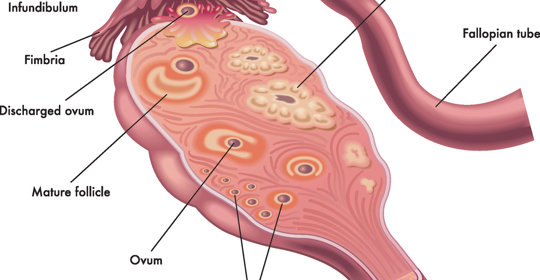

乳房腫塊:識別與防治

乳房腫塊:原因及治療措施

乳房腫塊:典型症徵與診斷方法

乳房腫塊:症狀、原因及診斷